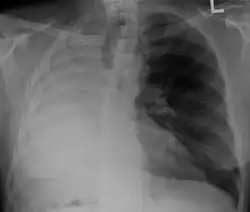

Tension pneumothorax

Tension pneumothorax is an emergent condition in which air gets trapped in the space between the chest wall and the lung. This space is referred to as the pleural space. Because air can't escape from this space, the air pocket grows larger and larger, resulting in the lung collapse closest to the pneumothorax. Forces are transmitted to the mediastinum and effectively "push" the mediastinal structures to the opposite side of the chest.[5]

Left tension pneumothorax with a large, well-demarcated area devoid of lung markings with tracheal deviation and movement of the heart away from the affected side.